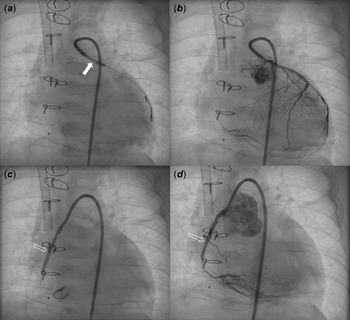

A male patient with d-transposition of the great arteries with an intact ventricular septum underwent arterial switch operation at 7 days of age. He had abnormal coronary arteries, both arising from a single coronary sinus, and an unusual left coronary artery with an intramural course. Both coronary arteries were re-implanted successfully by unroofing the left coronary artery ostium. One month after arterial switch operation, he presented to the emergency department with severe left ventricular dysfunction (left ventricle ejection fraction = 20%) and heart failure. Urgent coronary angiography confirmed severe stenosis of the proximal right coronary artery (Fig 1a) and near total occlusion of the left coronary artery ostium (Fig 1b). Emergent angioplasty of the left coronary artery ostium was performed in the 5-kg-body-weight patient. After post-operative recovery and improvement of left ventricular function, ventricular dysfunction (ejection fraction = 15%) re-developed at 4 months of age, approximately 2 months after the second operation. Percutaneous coronary intervention was planned in the infant, now 7 kg of body weight, to be performed by a paediatric cardiologist and adult interventional cardiologist. Elective extracorporeal membrane oxygenation of the right internal jugular vein-right common carotid artery was performed before percutaneous coronary intervention. Coronary angiography showed 95% segmental stenosis of the left coronary artery and 99% diffuse stenosis of the right coronary artery. Left coronary artery angioplasty with a 2.0 × 15-mm Maverick balloon was conducted successfully at 8 atm (Fig 2a), and 30% residual stenosis without dissection was confirmed (Fig 2b). Due to the unusual position of the right coronary artery, a 5-Fr JR 4.0 guiding catheter was reshaped and engaged properly with the right coronary artery. Runthrough and Sion guidewires were used to cross the lesion. Because 50% residual stenosis was found in the right coronary artery after angioplasty with 2.0 × 15-mm Maverick balloon at 12 atm, stent implantation with a 2.25 × 26-mm Orsiro stent at 12 atm was performed successfully (Fig 2c). After post-adjunctive balloon dilatation with 2.5 × 8-mm NC balloon, 10% residual stenosis in the right coronary artery was confirmed without dissection (Fig 2d). The total fluoroscopy time was 85 minutes. The patient was weaned successfully from extracorporeal membrane oxygenation the next day. Echocardiography at 7 days after percutaneous coronary intervention showed recovered ventricular contraction (left ventricle ejection fraction = 60%) but dilated left ventricle. The patient’s symptoms were relieved, and he was discharged on dual antiplatelet therapy with aspirin and clopidogrel. No complications related to femoral arterial cannulation in such a small patient were detected.

Figure 2. Coronary angiography after PCI showed balloon angioplasty (thick arrow) for LCA stenosis ( a ) with mild residual stenosis ( b ) and stent implantation (blank arrow) for RCA severe stenosis ( c ) with minimal residual stenosis ( d ). PCI: percutaneous coronary intervention, LCA: left coronary artery, RCA: right coronary artery.